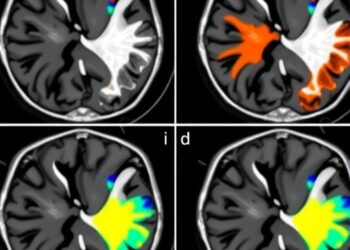

In recent years, the integration of artificial intelligence in the field of medical imaging has sparked a significant transformation, particularly ...